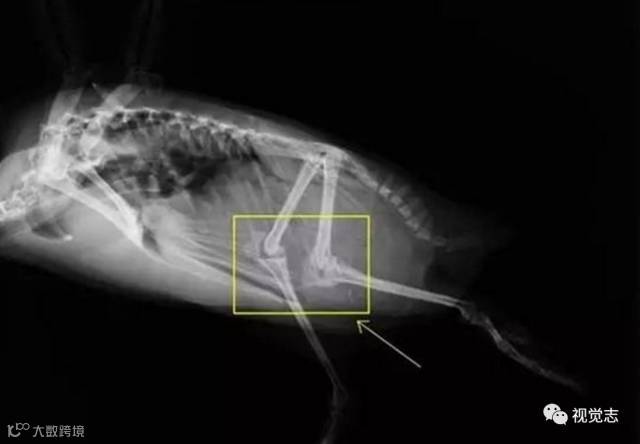

企鹅其实有一双大长腿。

▼